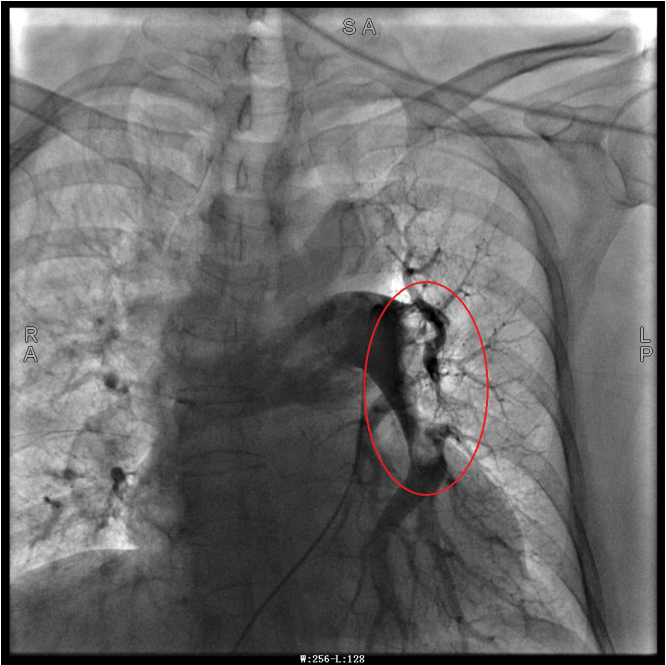

譚婆婆今年已經(jīng)72歲了,因“突發(fā)意識障礙2次”到璧山區(qū)人民醫(yī)院神經(jīng)內(nèi)科治療。譚婆婆沒有基礎(chǔ)心臟病病史,但近段時間活動耐量明顯下降,稍做活動就出現(xiàn)呼吸困難。入院后查BNP及心臟彩超均未提示明顯異常,查D二聚體明顯升高,經(jīng)心血管內(nèi)科周波醫(yī)師會診后轉(zhuǎn)入科室繼續(xù)治療。在心血管內(nèi)科主任、內(nèi)科學(xué)(心血管病)博士于長青的指導(dǎo)下,周波醫(yī)師成功完成醫(yī)院首例“一站式”微創(chuàng)介入手術(shù)。在影像中,可以清晰地看到堵塞的血管經(jīng)溶栓治療后,重新暢通無阻,流動起支撐生命的血液。

肺動脈造影技術(shù)是目前診斷肺動脈栓塞的“金標(biāo)準(zhǔn)”,在全程心電監(jiān)護下,通過股靜脈或者頸內(nèi)靜脈置入鞘管后,利用導(dǎo)絲引導(dǎo),將造影導(dǎo)管送入肺動脈;可在左/右肺動脈主干及其左右分支內(nèi),分別進行肺動脈造影或選擇性肺動脈造影,存在栓塞的肺動脈血管在造影劑注入后即會顯示出充盈缺損、充盈緩慢、或者血管顯影模糊,嚴重栓塞的肺動脈血管甚至?xí)霈F(xiàn)血流截斷征象。

注明:第一張、第二張為術(shù)前圖像